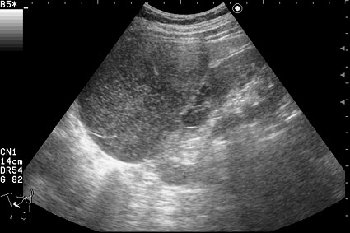

Изменения правой почки у женщины 55 лет

Периодически беспокоят несильные боли справа, чувство дискомфорта.

- Сонограмма правой почки.

Нет, это кистоподобное образование, связанное с почкой.

Необычнвя картинка. В голову приходят самые "сумашедшие" предположения (в т.ч. малигнизация кисты, но нет кровотока, нагноившаяся киста, но нет реакции ее стенки; киста с густым содержимым, но отчего оно так загустело?). Просветите нас, пожалуйста.

Почечно-клеточный рак правой почки, кистозная форма.